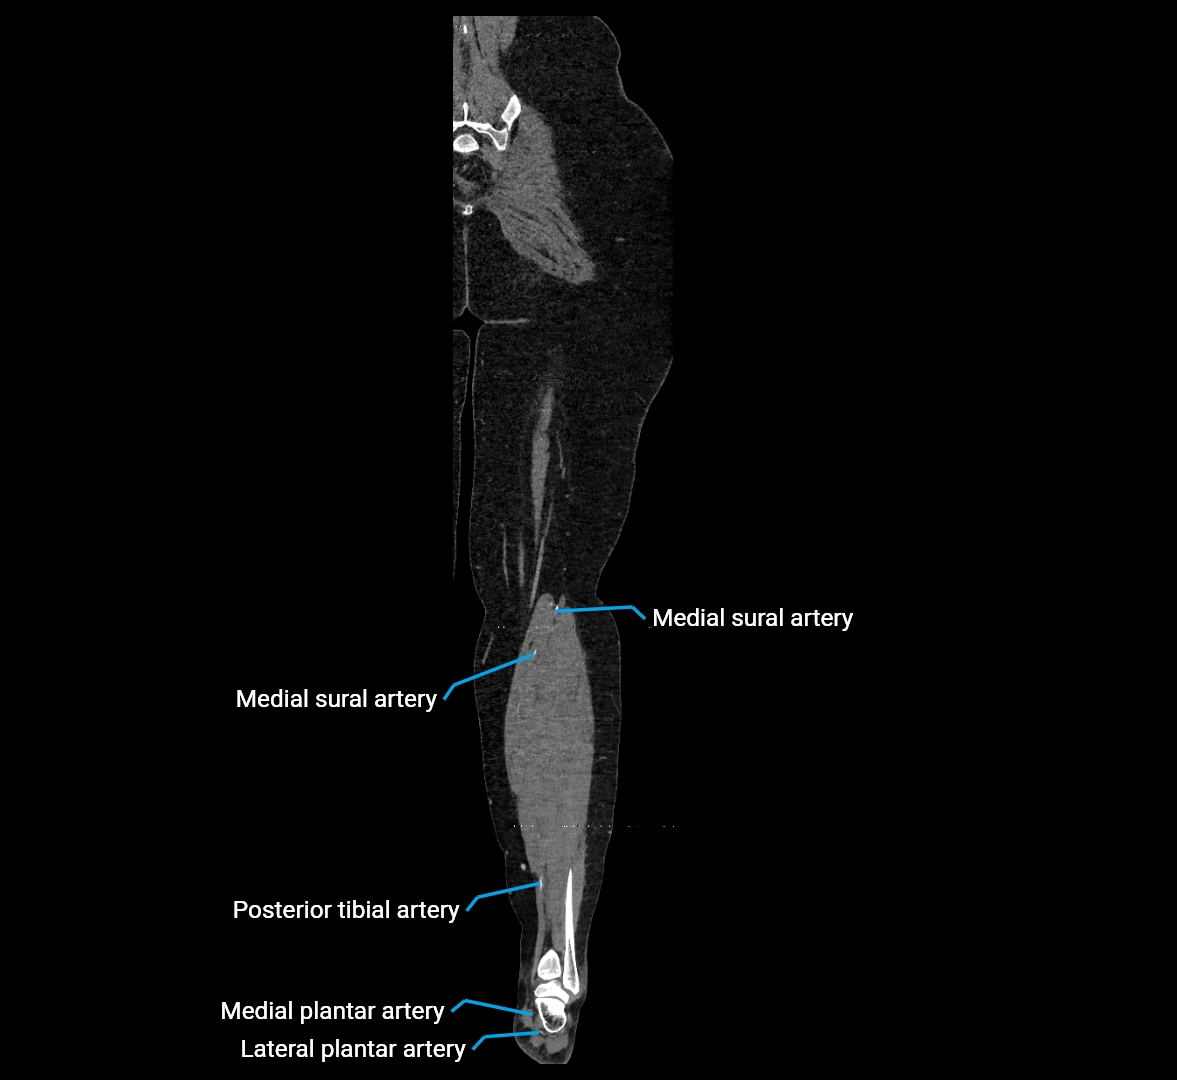

CT Appearance

Non-contrast CT:

• Appears as a tubular soft tissue structure anterior to vertebral bodies

• Calcified atherosclerotic plaques appear as hyperdense foci along the wall

• Useful for screening abdominal aortic aneurysm (AAA) size and mural calcification

Contrast-enhanced CT (CTA):

• Gold standard for abdominal aortic imaging

• Provides excellent detail of lumen, wall, aneurysm, thrombus, and branch vessels

• Multiplanar and 3D reconstructions help in aneurysm measurement, stent graft planning, and dissection evaluation

• Detects acute rupture, traumatic injury, or occlusion with high sensitivity